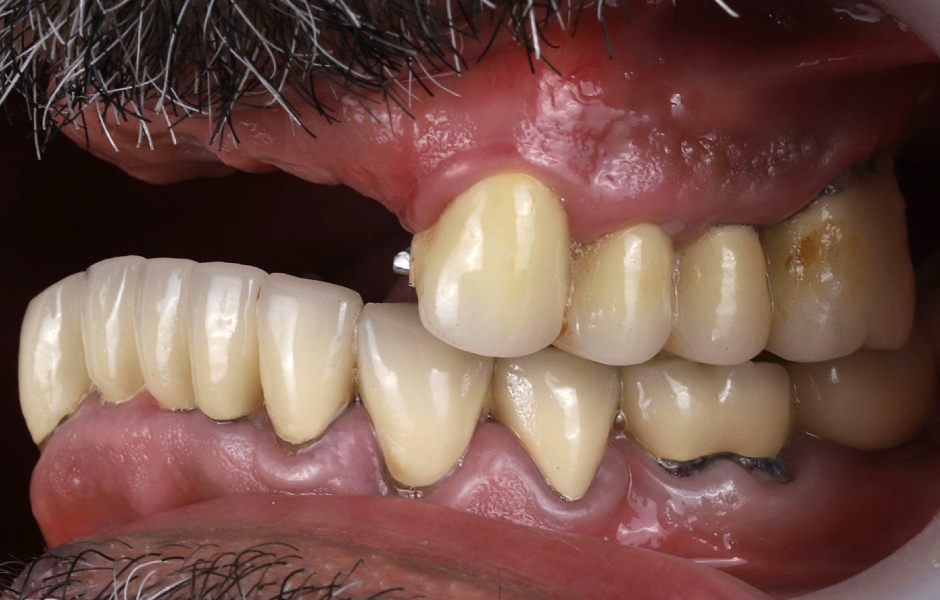

Při extraorální prohlídce nebyly zjištěny žádné významné abnormality. Pacient měl střední úroveň linie úsměvu (obr. 1–3). Po vyjmutí snímatelné náhrady byl odhalen můstek (obr. 4).

Intraorální vyšetření odhalilo starý můstek, který nahrazoval zuby 23 až 26 a zároveň sloužil ke kotvení částečné snímatelné náhrady s kovovou výztuží. Zuby 22 až 17 byly extrahovány již před delší dobou a alveolární hřeben v této oblasti byl zhojen. Nebyl přítomen plak ani zánět. Zuby vykazovaly mírnou až střední ztrátu attachmentu, ale nebyly pozorovány žádné parodontální léze nebo fraktury kořenů (obr. 5–8).

Obr. 1, 2

Obr. 3, 4

Obr. 5

Obr. 6

Obr. 7

Obr. 8